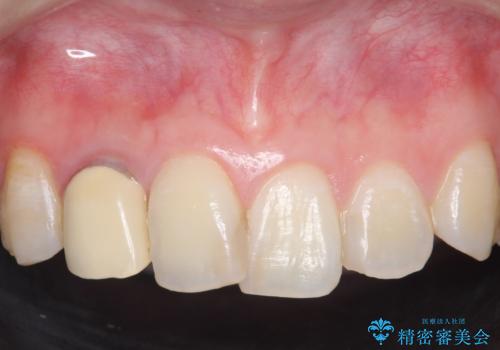

- 右上2番目の歯の被せ物と歯茎の間の継ぎ目が気になるといらっしゃった方の症例です。

再根管治療は希望されなかったため、クラウン除去後、オールセラミッククラウン(スペシャル)による補綴を行いました。

- オールセラミッククラウン(スペシャル)…¥130,000、仮歯…¥10,000、ファイバーコア…¥20,000費用は治療当時の料金となります